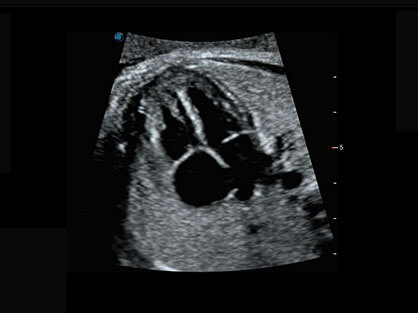

临床图

• AVC Follice卵泡自动测量

卵泡结构的自动识别和测量,可显示多组测量数据。